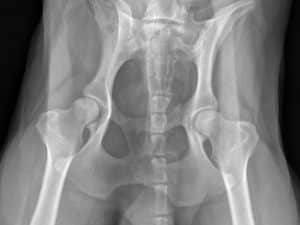

Oft wird eine Operation nötig mit dem Ziel den Körper in einen möglichst physiologischen Zustand zurückzuversetzen. Was aber genau ändert sich durch den operativen Eingriff und worauf ist danach, für ein bewegtes Hundeleben, zu achten?

Wir beschäftigen uns jeweils mit der physiologischen funktionellen Anatomie der Gelenke samt Muskulatur, um Veränderungen verstehen und behandeln zu können.

Daraus wird ersichtlich welche funktionellen Eigenschaften, beispielsweise das Kreuzband, in einem gesunden Kniegelenk hat und welche Muskulatur aufgebaut werden muss um das Gelenk, nach Kreuzbandriss, vor übermäßigem Schaden zu bewahren!

Danach betrachten wir die Veränderungen die die häufigsten orthopädischen Pathologien und gängigsten Operationsmethoden mit sich bringen um zu entscheiden welche Maßnahmen während der Rekonvaleszenz vonnöten sind um einer Heilung nicht im Wege zu stehen, gezielten Bewegungs- und Muskelaufbau entsprechend der Defizite zu betreiben und dem Besitzer Gebote und Verbote für den zukünftigen Alltag seines Vierbeiners zu erteilen.